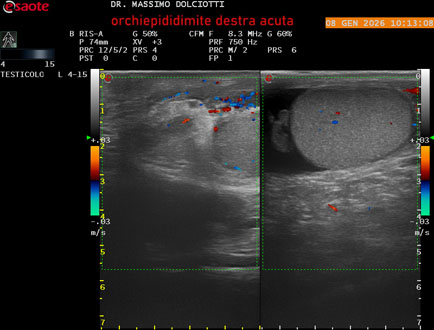

Data inserimento: 08/01/2026

Ecografia del: 08/01/2026

Strumento: Esaote MyLab Eight

Sonda: Lineare Multifrequenza 4-15 MHz

Età Paziente: M 74 anni

Motivazione dell'esame: da 3 giorni dolore e tumefazione al testicolo destro.

Commento all'esame: le immagini ed il video documentano il didimo destro, aumentato di volume, con incremento della vascolarizzazione; aumentato di volume e di vascolarizzazione anche l'epididimo destro, Normale il didimo sin e l'epididimo sinistro, Gli elementi ecografici segnalati orientano per orchiepididimite destra acuta.

Conclusioni: orchiepididimite destra acuta (right acute orchiepididymitis).

Presentazione: Dr. Massimo Dolciotti - Ancona